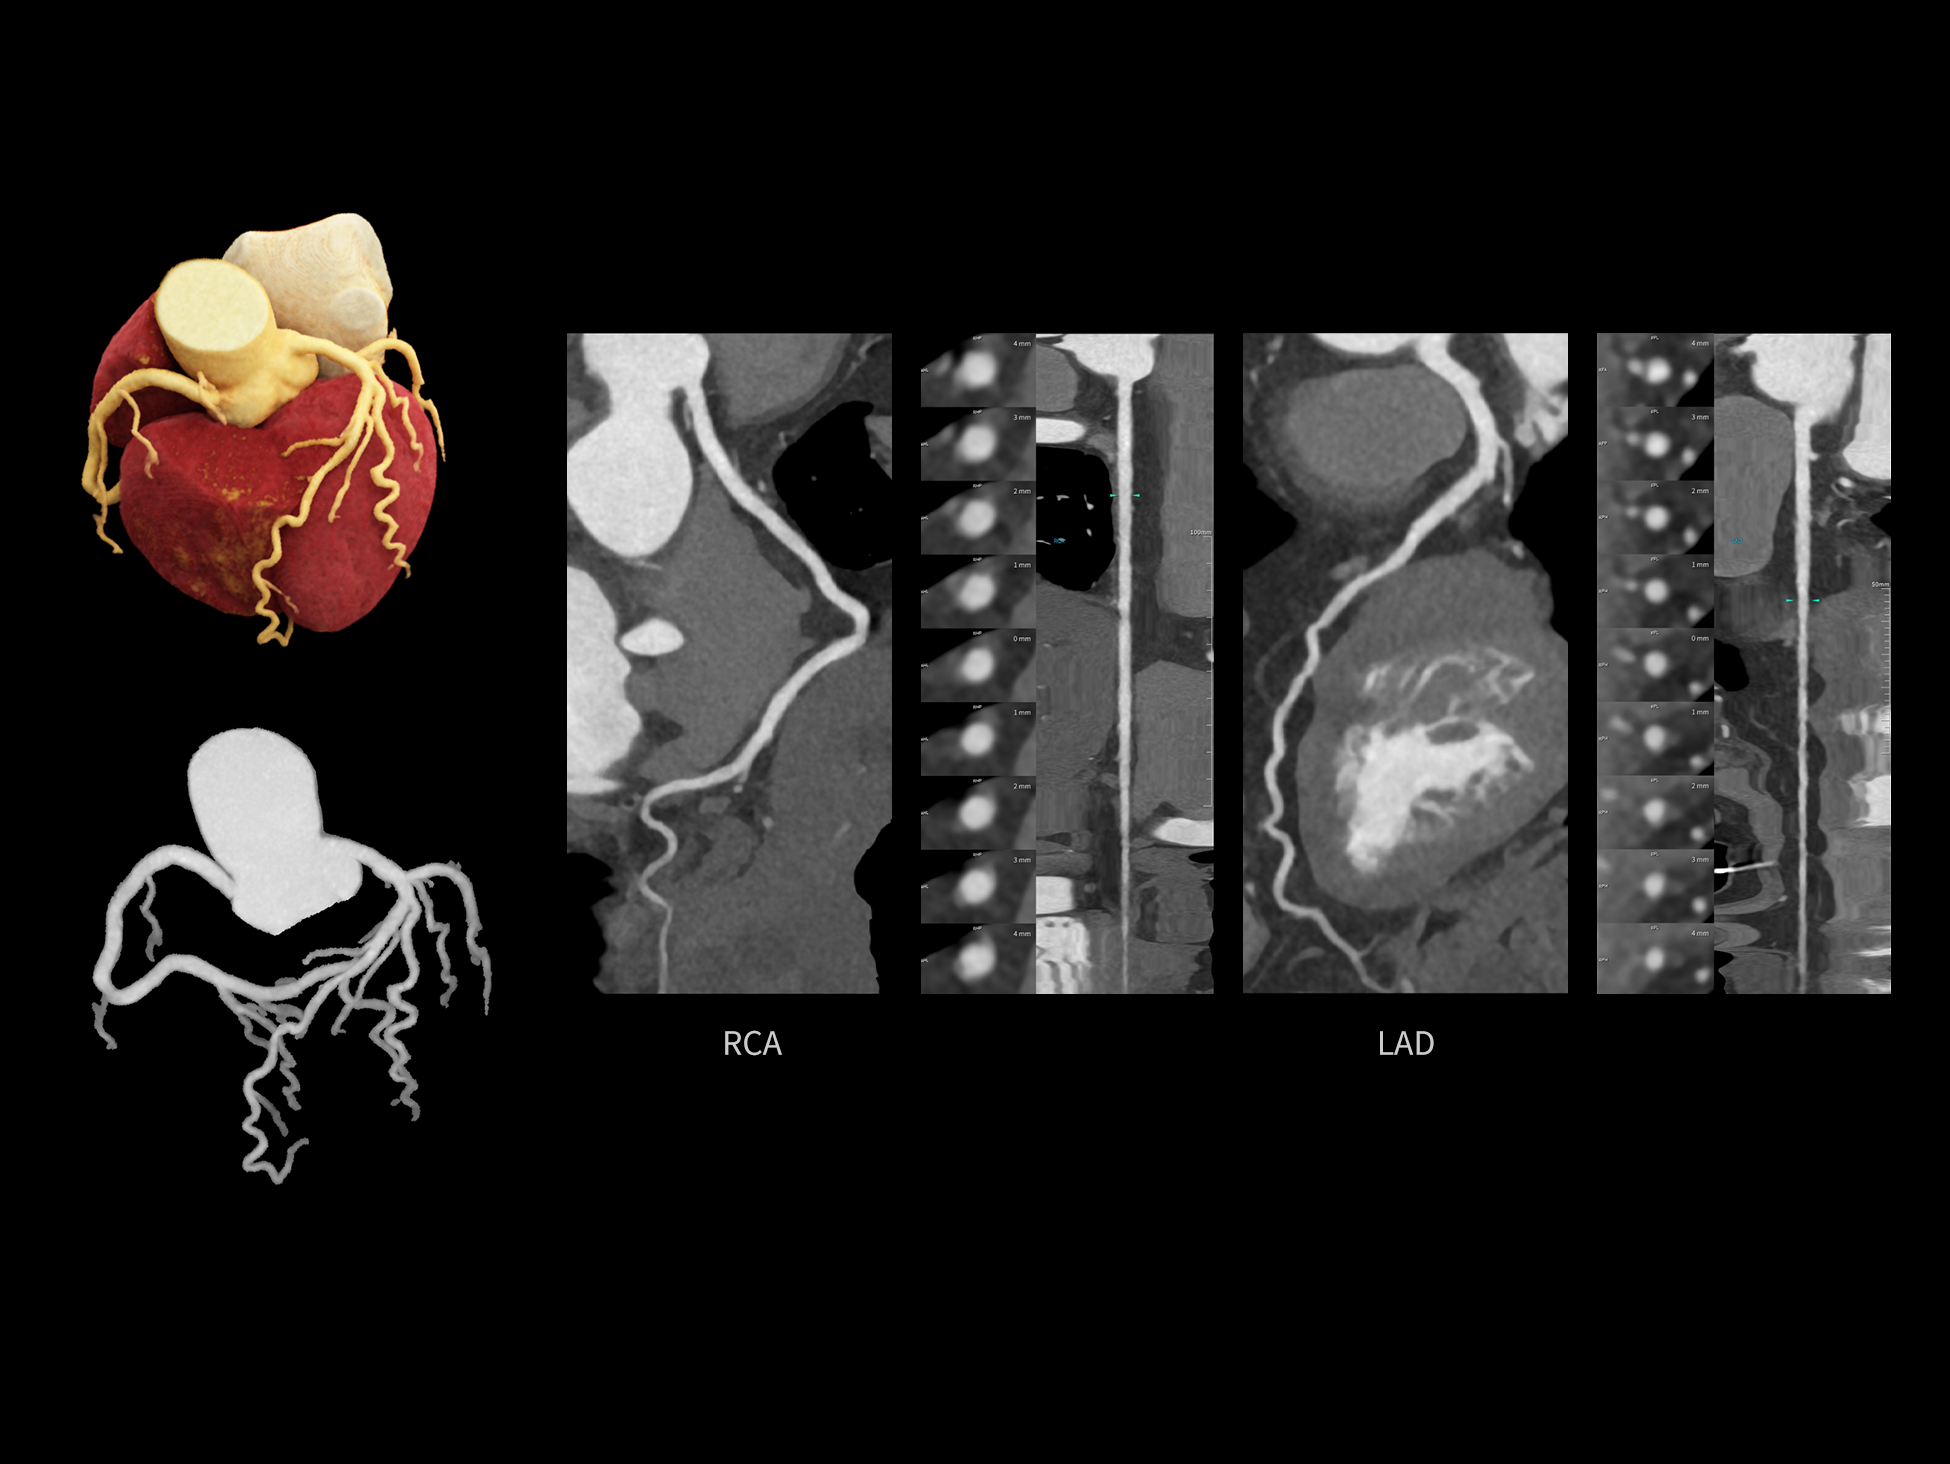

全时心脏

uCT SiriuX® 挑战心脏成像时间分辨率的极限,精准捕捉心脏全周期的动态变化。无论静态解剖形态,还是动态功能表现,都能清晰呈现,让心脏不再是“定格”的器官,而成为可视的生命律动。

突破全心时间分辨率极限

CardioCapture 2.0 通过“识别–追踪–建模–校正”的完整流程,精准分割心脏结构,动态追踪运动轨迹,并构建多时相运动场,最终实现冠脉、瓣膜、心肌及心室结构的同步校正,清晰洞见每一次心跳细微变化,真正将心脏动态掌握于毫秒之间。

CardioCapture 2.0 在目标时相前后重建多时相影像,通过深度学习网络精准提取冠脉中心线,进而建立时相间运动模型,实现对冠脉分段图像的精准运动校正。

冠脉运动校正

心脏成像,自由掌控

uCT SiriuX® 以 8ms 全心等效时间分辨率与16cm宽体覆盖,突破传统心脏成像局限,完整呈现搏动中的心脏结构与动态功能;配合无心电门控扫描与智能化工作流,更使心脏检查摆脱心率、配合度与操作复杂度的束缚,实现真正自由从容的成像体验,为临床功能评估提供更深层依据。

全心全时相高清成像

单心动周期内的任意时相获取高质量的冠脉CTA图像,确保稳定的心脏成像效果。